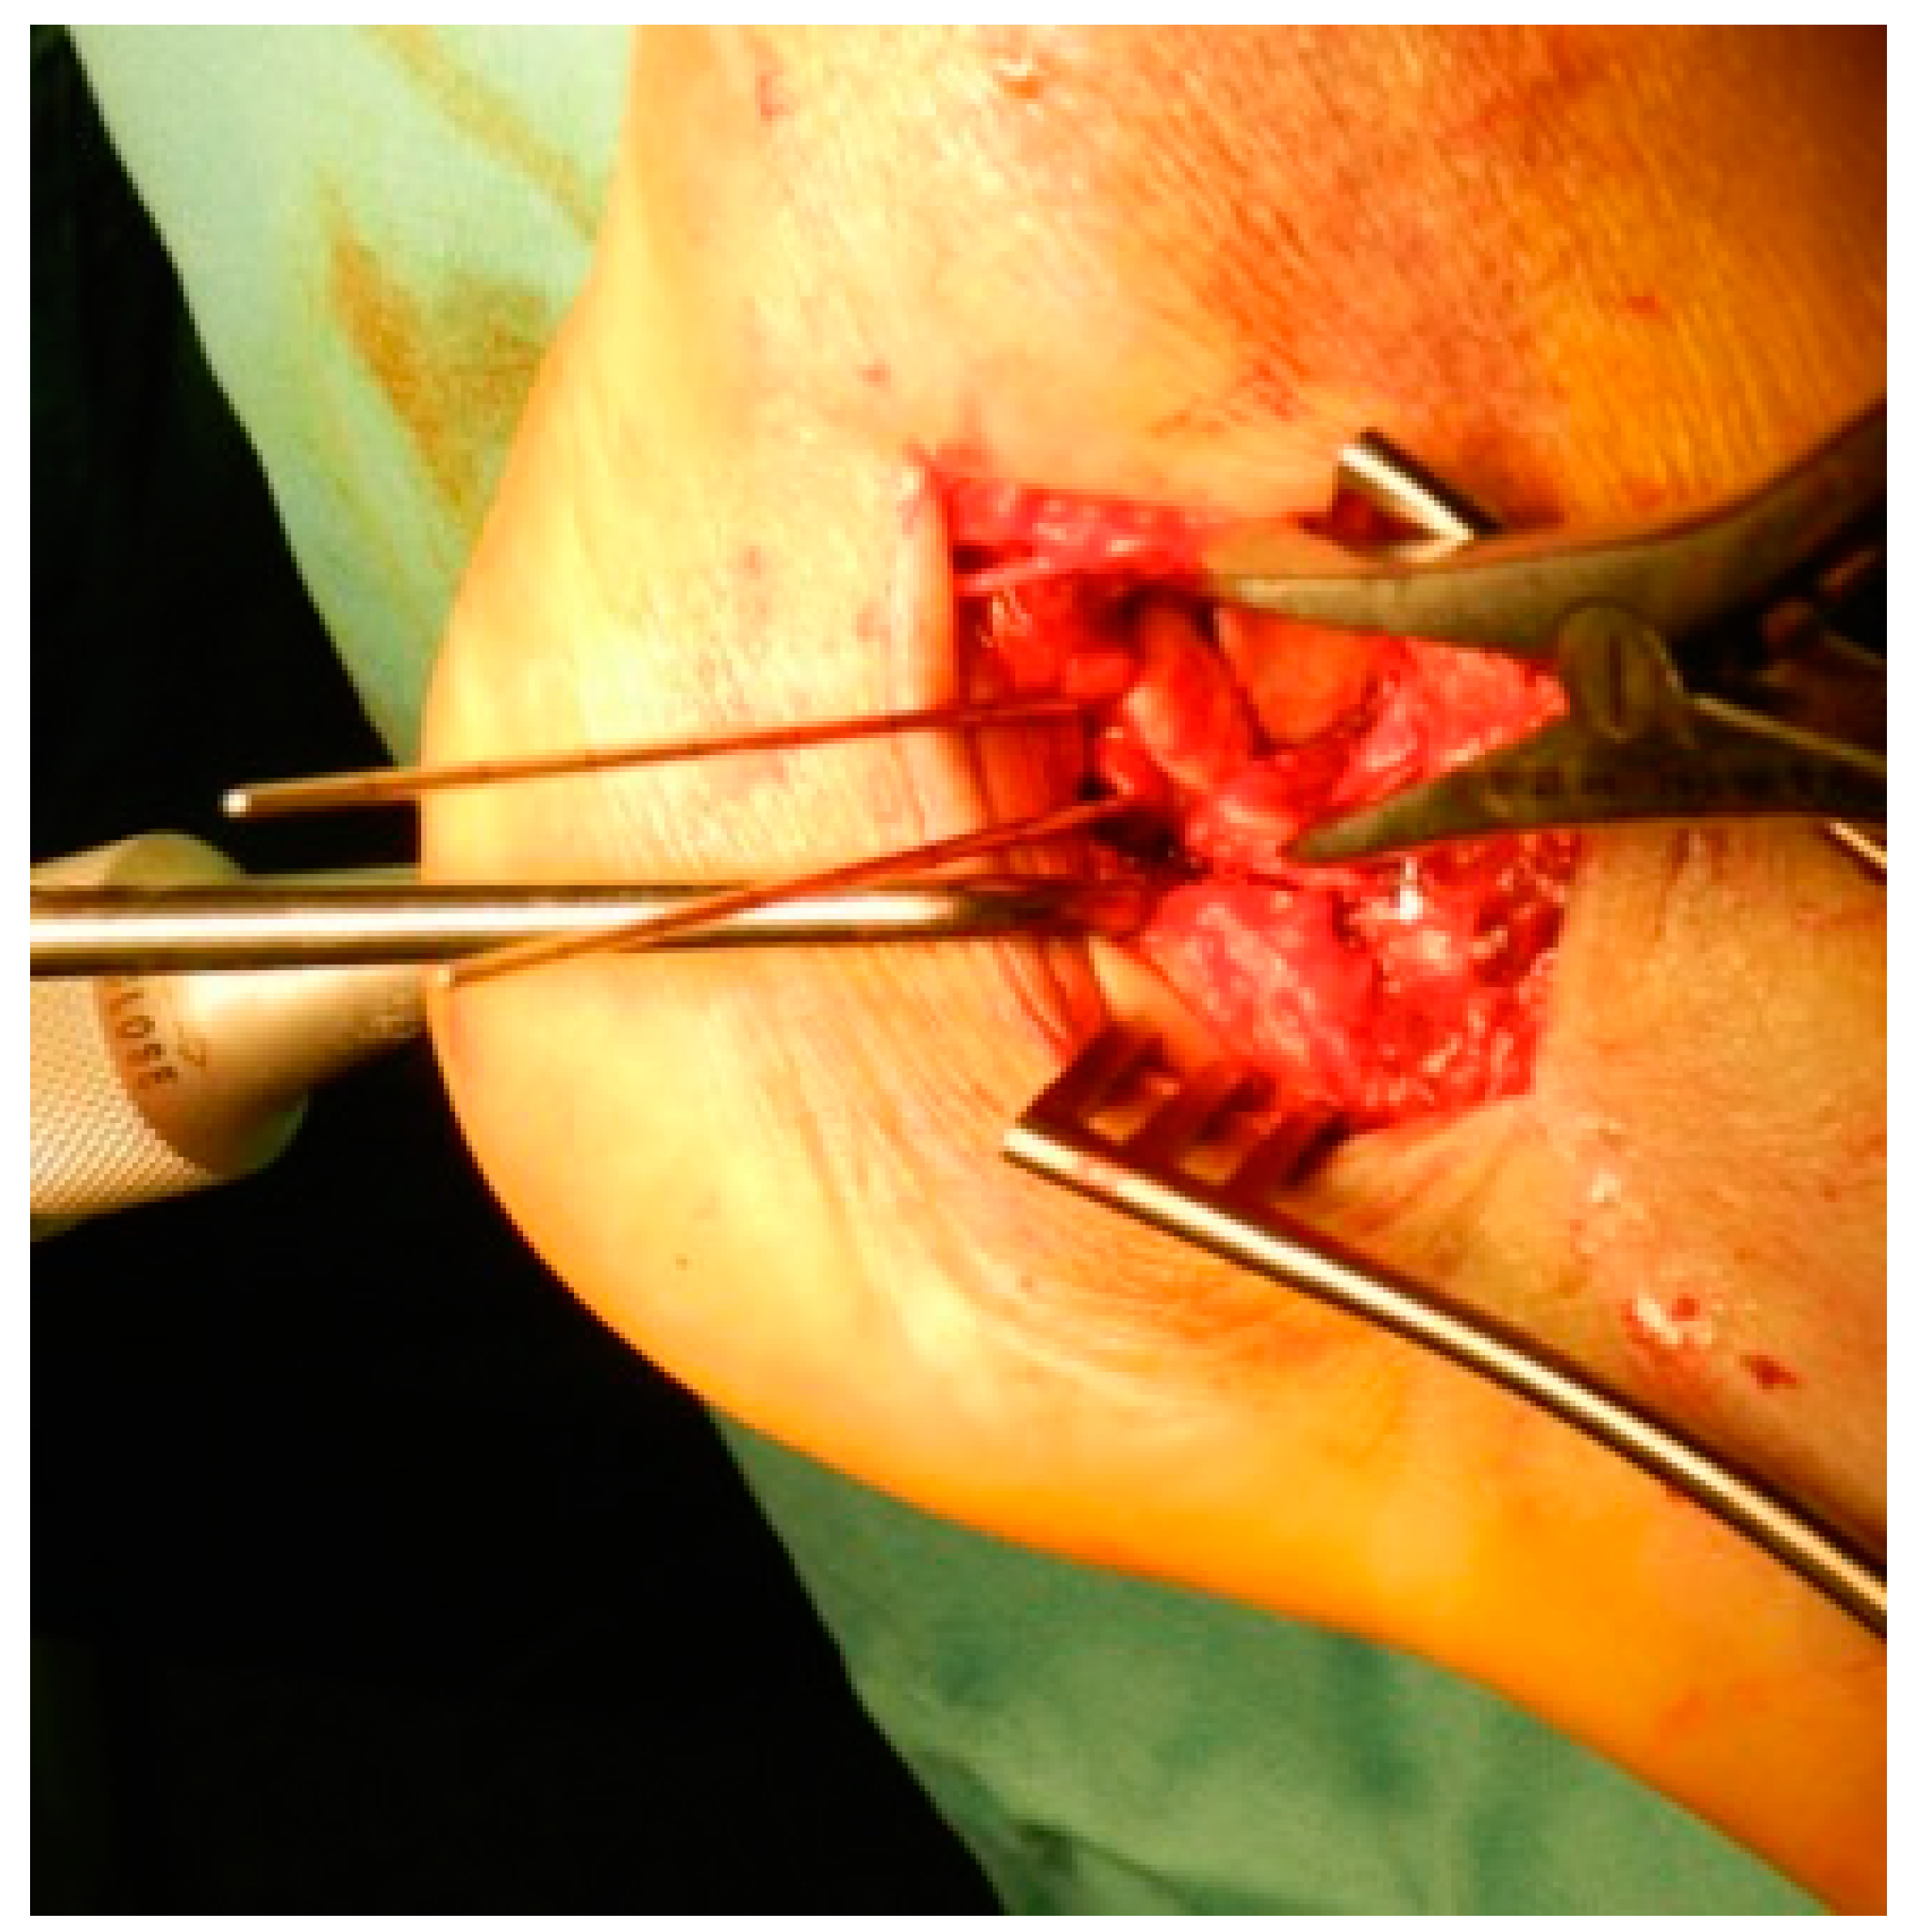

| Fragments exposure | Release of the inferior peroneal retinaculum Release of the CFL and subtalar ligaments SJ exposure |

| Steps for fragments reduction | Reduction of the PT fragment to the sustentacular constant fragment Reduction of articular fragments from posterior to anterior |

| Osteosynthesis | Temporary fixation with K-wires IF with plate and screws |